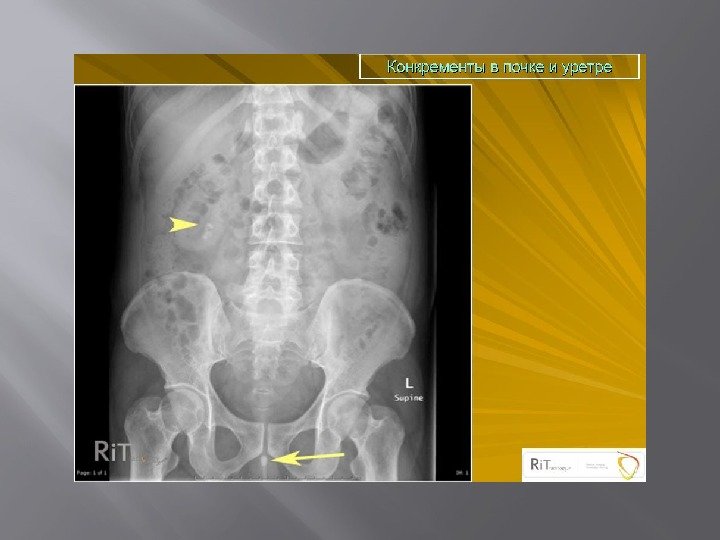

Обзорная урография Тень поясничных мышц в норме на рентгенограмме имеет вид усеченной пирамиды, вершина которой расположена на уровне тела XII грудного позвонка. Изменение контуров или исчезновение тени этих мышц может быть признаком патологического процесса в забрюшинном пространстве. Неизмененные мочеточники на обзорном снимке не видны. Тень мочевого пузыря, наполненного мочой, имеет форму эллипса. Добавочные, т. е. патологические, тени могут быть самыми разнообразными и относиться к различным органам и тканям. Любую тень, имеющую ту или иную степень плотности и находящуюся в зоне расположения мочевых путей, следует трактовать как возможный конкремент. Часто тени в проекции таза обусловлены флеболитами — венными камнями, обызвествленными фиброматозными узлами матки или обызвествленными сосудами. Решить вопрос об отношении обнаруженной тени к мочевым путям можно с помощью рентгеноконтрастных методов исследования.

Мочекаменная болезнь

Мочекаменная болезнь ХРОНИЧЕСКИ ПРОТЕКАЮЩЕЕ ЗАБОЛЕВАНИЕ ХАРАКТЕРИЗУЮЩЕЕСЯ НАЛИЧИЕМ В ПОЛОСТНОЙ СИСТЕМЕ ИЛИ ПАРЕНХИМЕ КАМНЕЙ, ФОРМИРУЮЩИХСЯ ИЗ СОСТАВНЫХ ЧАСТЕЙ МОЧИ. Составляют 30 -40% всех хирургических заболеваний. Различают одиночный камень, множественные лоханочные и комбинации лоханочного камня с чашечковым или поренхиматозными. Выделяют понятие рентгенонегативного камня, т. е. камень который не даёт тени на рентгенограмме.

Экскреторная урография -рентгненегативные камни- дефект наполнения — Рентгенпозитивные камни-тень камня усиливается